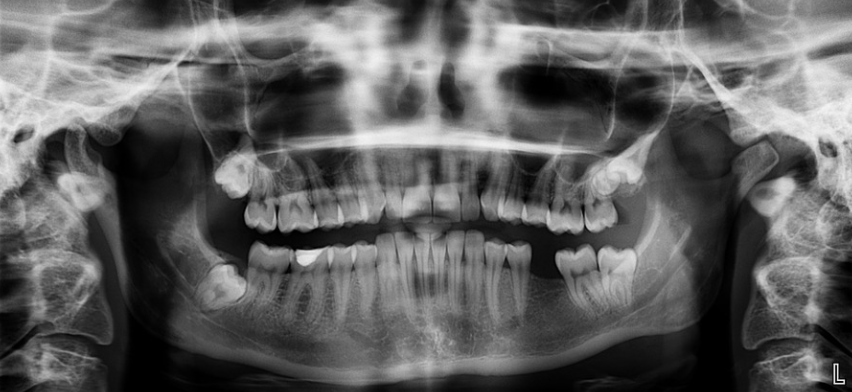

Рентген